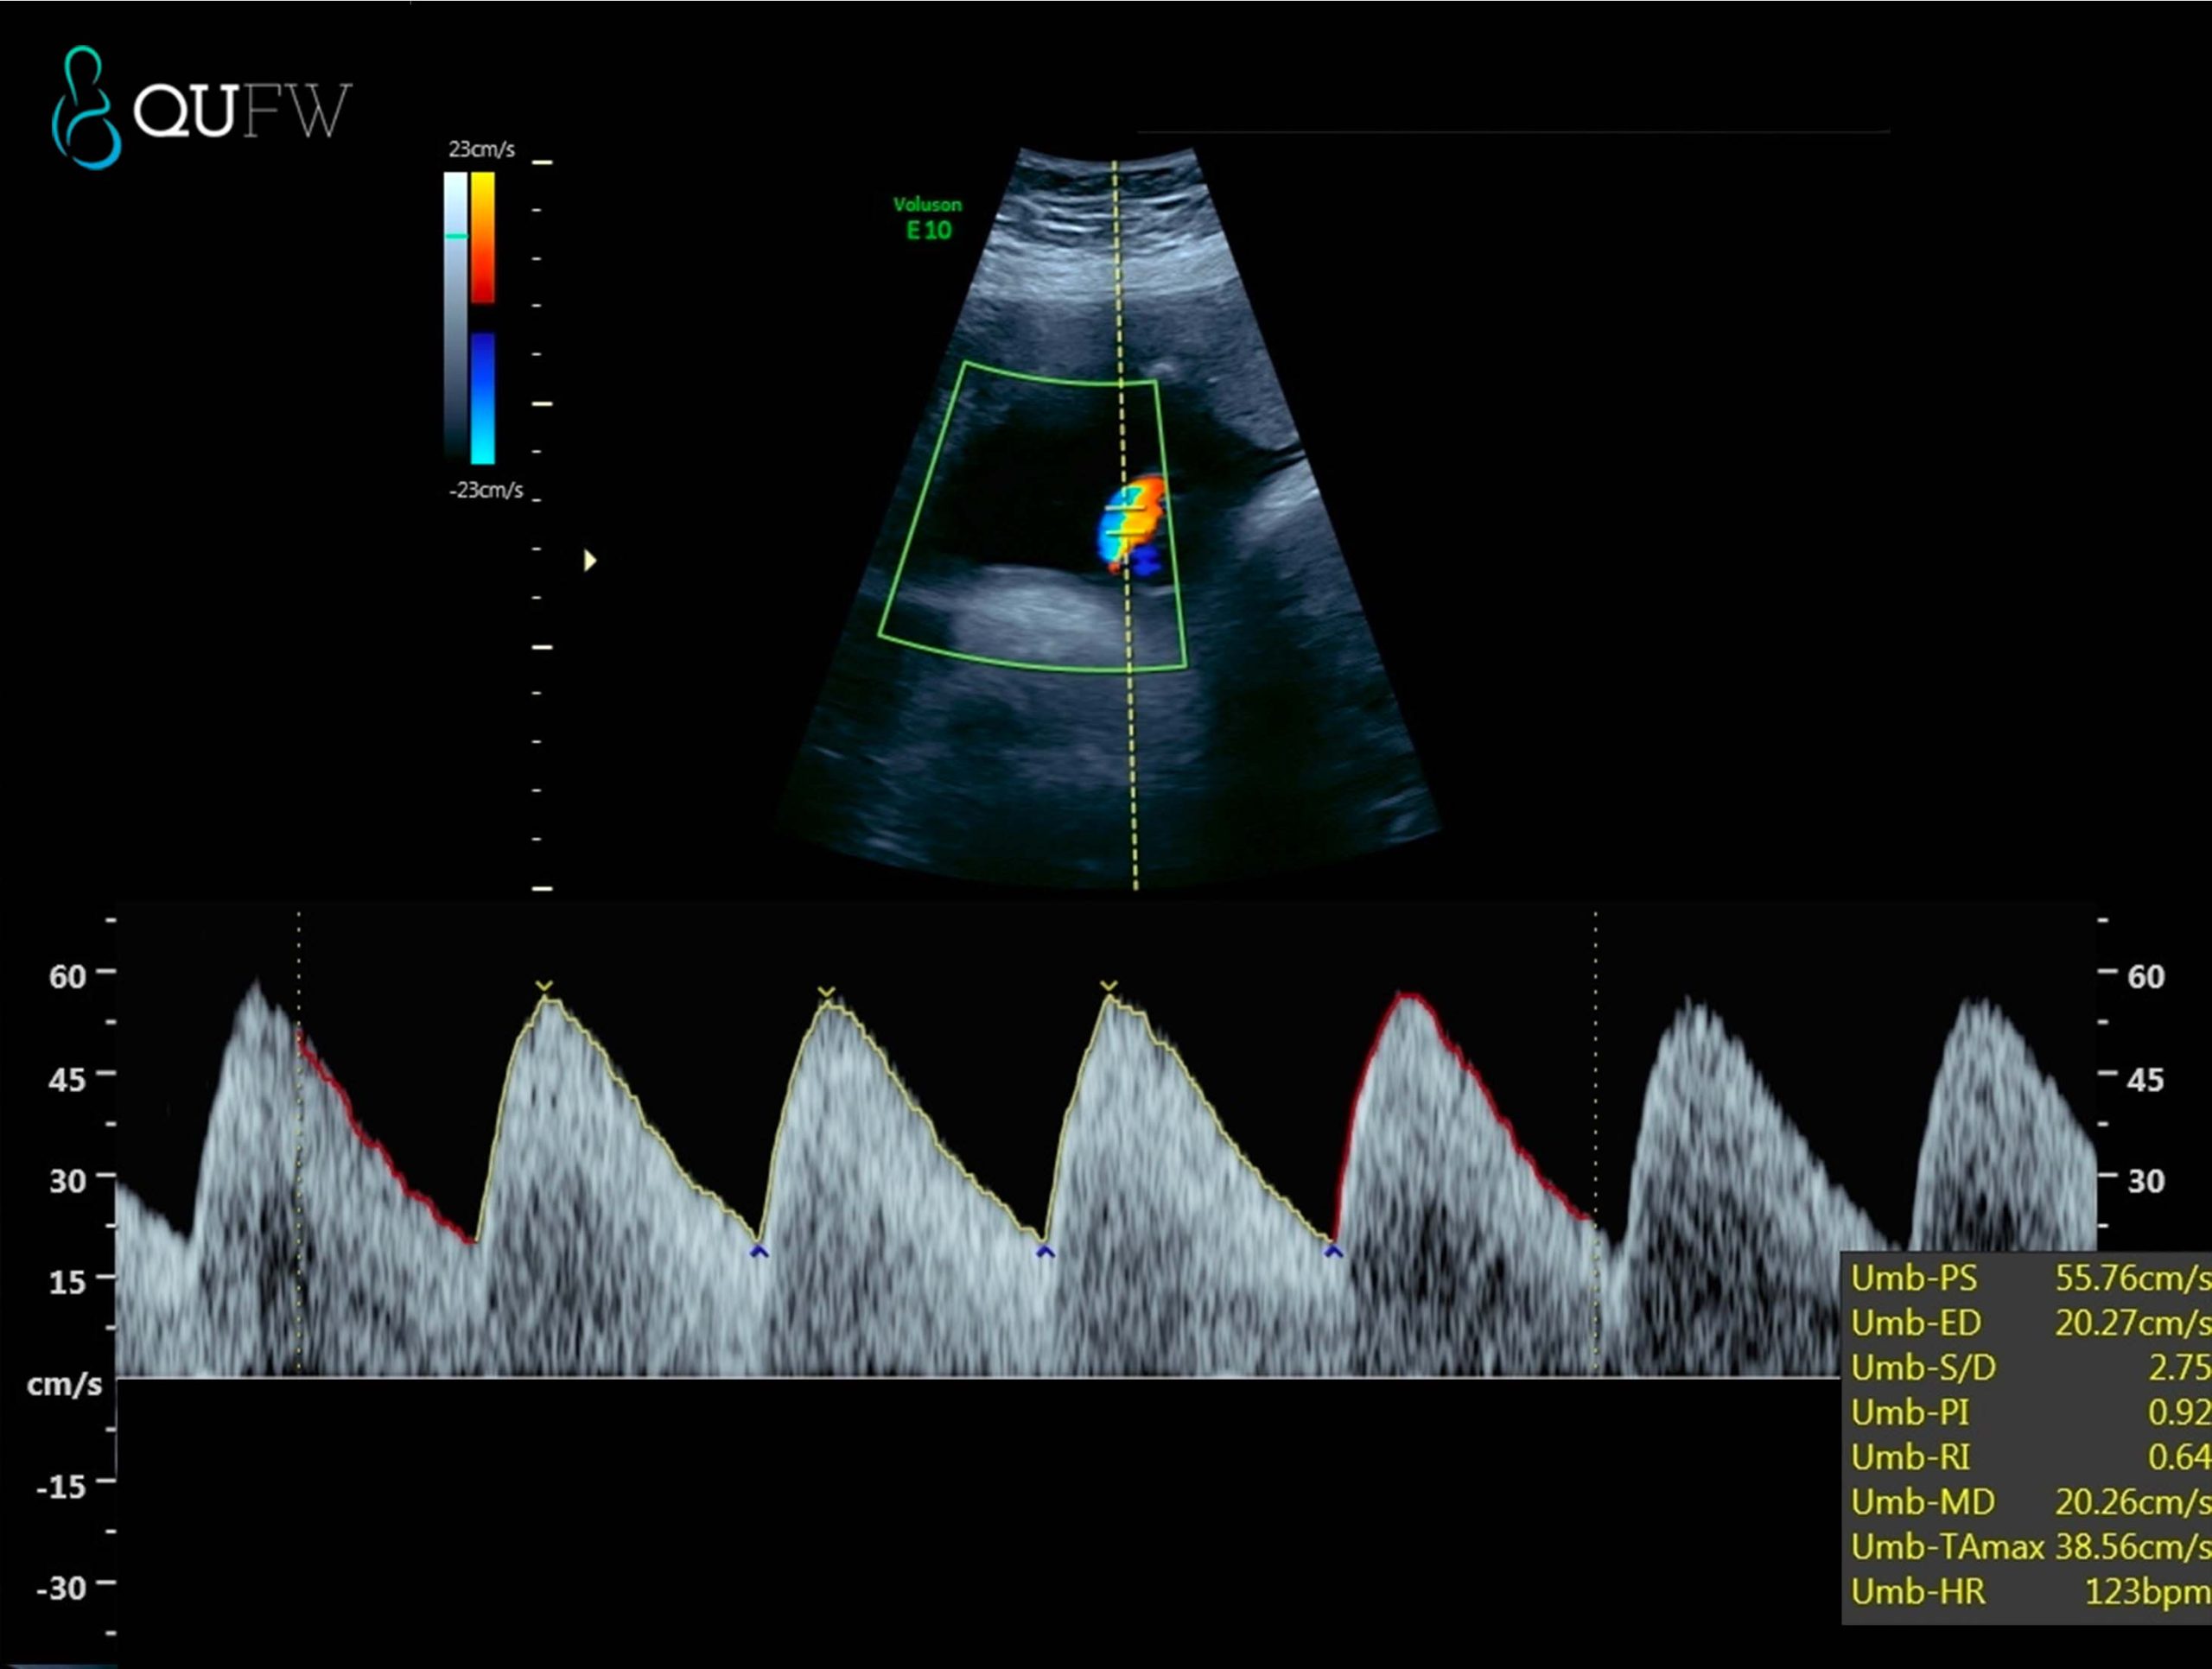

An important aspect of the scan is assessing the function of the placenta, the organ that provides your baby with nutrients and oxygen. By looking at the blood flow in the umbilical cord and around the placenta, the ultrasound can help determine whether your baby is receiving an adequate supply of nutrients and oxygen. Reduced blood flow could indicate problems like placental insufficiency, which might require close monitoring or early delivery.

Umbilical artery Doppler assessment for placental and fetal wellbeing